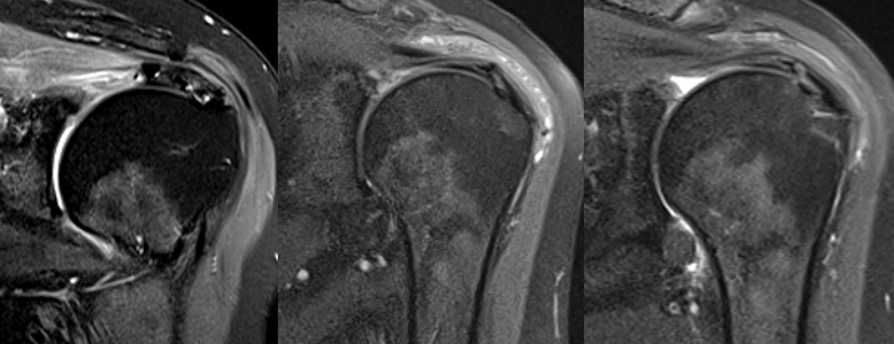

Preoperative RTC tear type and dimensions are listed in Table 2. At both 3 and 6 months postoperatively, each patient underwent MRI evaluation of the affected shoulder. No recurrent rotator cuff tears, failure of the repairs, or effusions were identified (Table 2). The rotator cuff footprint was restored in each case (Table 2). All patients showed early tissue reactions at the 3-month mark in the subacromial space, with thickened tissue corresponding to the area where the HA patch had been placed. By 6 months postoperatively, the amount of reactive bursal tissue and edema had decreased, and the tendon-like tissue continued to organize, maintaining its thickness. All full-thickness RTC tears (n=6) as well as all four “onlay” procedures (n=3 partial thickness, n=1 myotendinous) were healed by 6 months (Table 2). The average tendon thickness at 3 months postoperatively was 7.63 ± 1.30 mm, and by 6 months, it remained stable at 7.61 ± 1.03 mm, both significantly increased from preop thickness of 4.77 ± 0.67 (p<0.001) (Table 3). These findings suggest successful integration of the HA patch and healing of the repaired tendon.

Our study demonstrated early safety and efficacy of the first HA based rotator cuff graft with improvement in all PROMs and no complications. Postoperative MRI showed healed RTC, footprint restoration, and significantly increased tendon thickness similar to a popular Bovine patch (Bokor et al. 2016; 2015). Subacromial reactive changes were seen in all patients at 3 months and resolved with tendinous incorporation and thickening by 6 months (Tables 2 and 3). Although this is very early follow-up, it is important to ensure this new technology is both safe and effective, as there have now been more than 1000 surgical implantations throughout the US (Baker 2025).

Thickening of the rotator cuff tendon either by healing of the tendon itself or by integration of tendon-like tissue is felt to be the main benefit of supplementing RTC repairs with a bursal sided patch (Bokor et al. 2016; 2015). It has been the senior author’s experience that the use of various synthetic and biologic graft augmentations in RTC repair leads to early postoperative reactive “inflammatory like reactions” in the subacromial space. A previous study on the Integrity Implant System in an Ovine model showed progressive implant degradation along with fibroblast neocollagen deposition, and fiber-like organization around the PET component within the RTC throughout the 26 week study (Badylak 2023).

This study revealed similar reactive subacromial changes on postoperative MRI, which likely reflects the graft’s biodegradation and cell mediated immune response corresponding to T2 edema on MRI at 3 months postop (Figures 4 and 5). However, there was ultimate thickening and consolidation of this edematous area into low signal tendon-like tissue in the RTC at 6 months, which may indicate a completed healing response, and partial degradation and structural incorporation of the graft. This study also shows similar thickening and healing of both partial thickness and full thickness RTC tear patients, with ultimate consolidation into a single continuous tendon complex. Previous studies measuring RTC tendon thickness after repair in the absence of patch augmentation most commonly show reduced tendon thickness compared to preoperative ipsilateral as well as contralateral measurements (Kjaer et al. 2024; Crim et al. 2010; Tham et al. 2013). However, one study reported a small proportion of patients did undergo tendon thickening compared to preoperatively (Crim et al. 2010). It was felt important to characterize the expected imaging characteristics of the HA patch in short intervals of 3 and 6 months postop to inform physicians of the thickened subacromial appearance and investigate tendinous healing and graft incorporation radiologically. We reported significant increase in average tendon thickness from 4.77 ± 0.67 mm to 7.63 ± 1.30 mm at 3 months (p<0.001), and 7.61 ± 1.03 mm at 6 months (p<0.001), which is similar to published data for a commonly used bovine collagen patch that reported mean tendon thickness at 6 months postop as 7.6 mm for men and 7.0 mm for women (Bokor et al. 2015). This is noticeably thicker than ultrasound measured supraspinatus thickness at the same timepoint, being 5.6 mm for men and 4.9 mm for women on average (Karthikeyan et al. 2014).